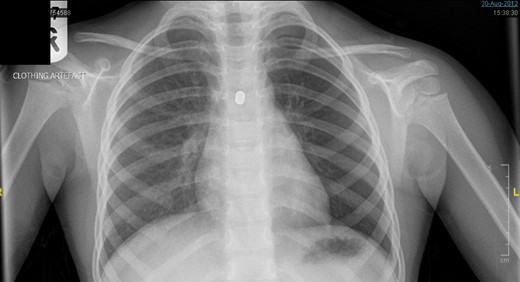

A ventilating bronchoscopy was performed by the otolaryngology team where the FB was found to be stuck to the posterior wall of the left main bronchus. The FB was left in-situ. After the operation, a lateral CXR (Fig. 3) illustrated the metallic FB appeared to be two spherical balls, with the anterior one in the left main bronchus and the posterior one in the oesophagus. A subsequent further history from the parents suggested these were from the older sibling’s toys.

Lateral CXR showed the metallic foreign body to be two spherical balls, with the anterior one in the left main bronchus and the posterior one in the oesophagus.